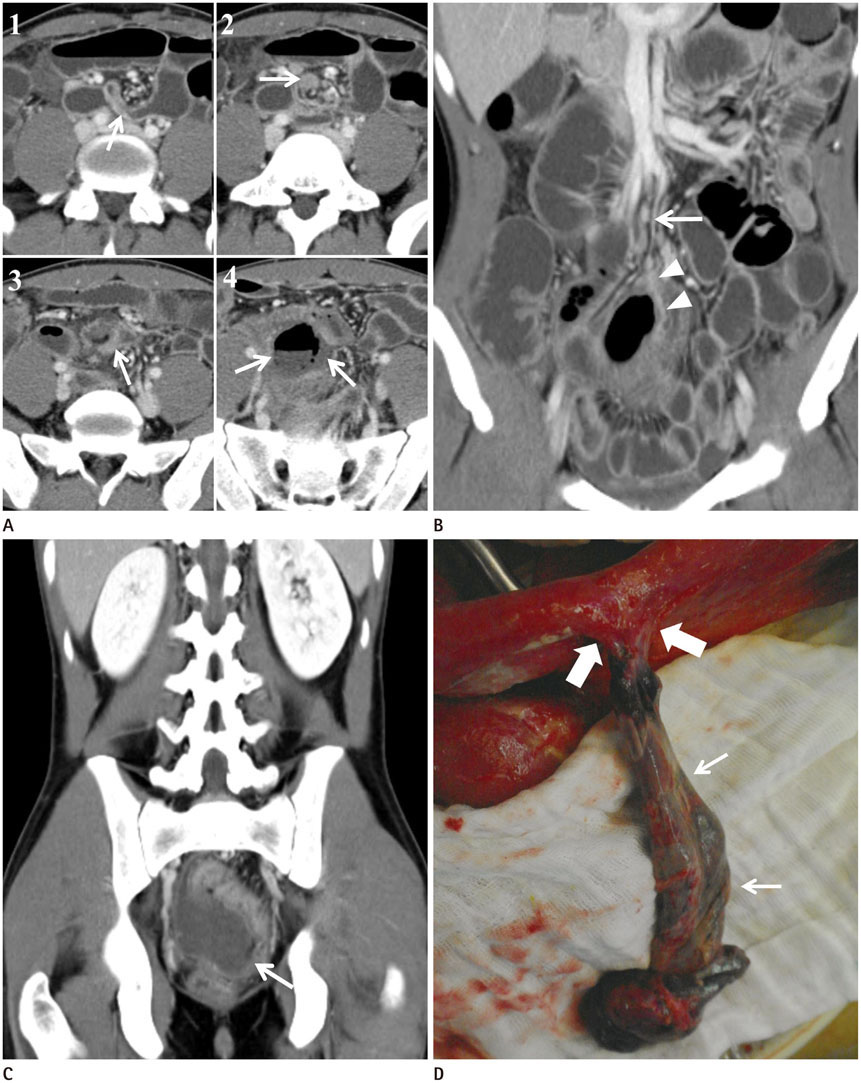

Axial Torsion of Meckel's Diverticulum Causing Small Bowel Obstruction in Adult: A Case Report

- Meckel's diverticulum (MD) is the most common congenital abnormality of the gastrointestinal tract that is prevalent in 2-3% of the population. The lifetime risk of complications is estimated at 4%. Small bowel obstruction is the second most common complication of MD. Among the causes of bowel obstruction, axial torsion of MD is the rarest complication. Urgent surgical treatment is needed in cases of small bowel obstruction associated with torsion of MD. Pre-operative diagnosis of MD as a cause of small bowel obstruction is difficult, because the diagnosis can be made only if the diverticulum is delineated at the site of obstruction. We reported a case of axial torsion of MD with necrosis that caused proximal small bowel perforation in a 21-year-old male.